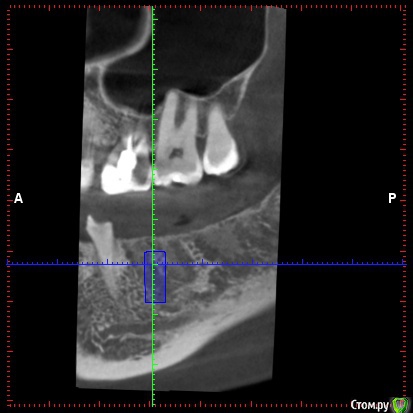

DenisV Опубликовано 22 мая, 2018 Поделиться Опубликовано 22 мая, 2018 Уважаемые коллеги, подскажите советом, допустимо ли с вестибулярной стороны 1.5мм кортикальной кости, или лучше НКР? на фото имплант 4.3*10? Ссылка на комментарий